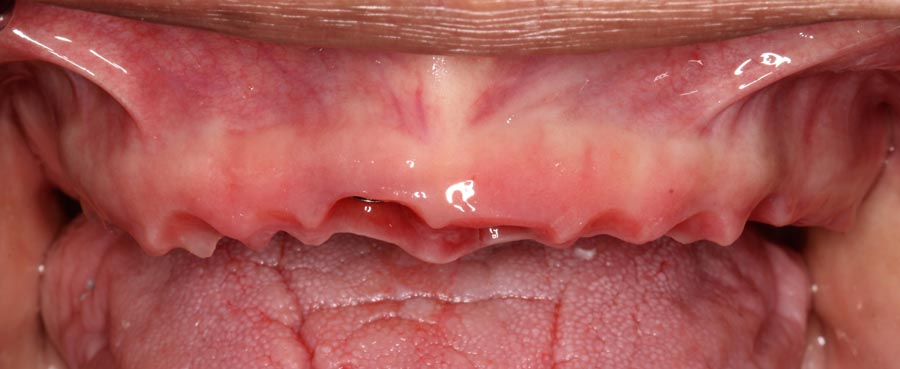

Smile GalleryImplant RestorationsFull Mouth Implant Restoration Full arch zirconia implant bridge (full smile) 1 of 37 Pre-op full smile Pre-op lips retracted Pre-op panoramic x-ray Extraction of strategic teeth Placement of implants Extraction of some remaining teeth after verification of adequate implant stability Occlusal view Post-op panoramic x-ray Immediately fabricated provisional restoration (tissue side view) Immediately fabricated provisional restoration (occlusal side view) Immediate provisional delivered on day of surgery Immediate provisional 2 weeks later Scalloped tissue developed from the provisional at 2 weeks Jig used for making a master impression Provisional in place (full smile) Provisional in place (lips retracted) Provisional in place (right side) Provisional in place (left side) Wax try-in (full smile) Wax try-in (right side full smile) Wax try-in (left side full smile) Wax try-in (full face, lips together) Wax try-in (full smile) Wax try-in (right side) Wax try-in (left side) Wax try-in (lips retracted) Full arch zirconia implant bridge on master cast (frontal view) Full arch zirconia implant bridge on master cast (occlusal view) Implant positions and soft tissue representation on master cast (occlusal view) Soft tissue representation on master cast (frontal view) Full arch zirconia implant bridge (tissue side view) Soft tissues on day of delivery (occlusal view) Soft tissues on day of delivery (frontal view) Full arch zirconia implant bridge delivered (lips retracted) Full arch zirconia implant bridge (lips retracted, close up) Post treatment panoramic x-ray Full arch zirconia implant bridge (full smile)